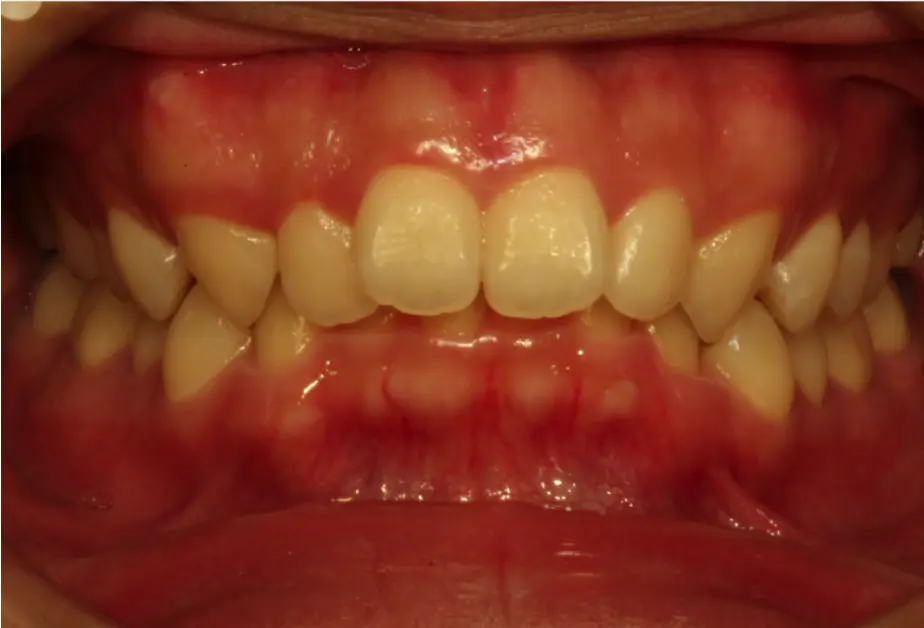

A deep bite—also called an excessive overbite—is when the upper front teeth overlap the lower front teeth significantly, often covering them almost entirely. It’s more than just a cosmetic concern: deep bite can affect chewing, speech, jaw health, and overall facial harmony. Severity ranges from mild to pronounced, and early detection allows simpler, more predictable treatment.